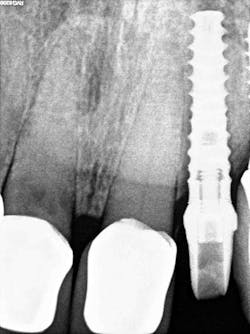

Second visit: After two months of healing, final impressions were taken.

The implant was allowed to heal for two months before impressions were taken. The final zirconia crown was delivered two weeks later (figure 6).